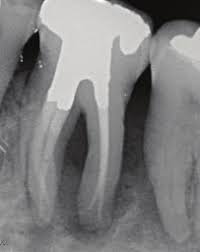

الضرس بعد التحضير

خلصت دراسة الى أفضلية عمل تلبيس Crown للاضراس المعالجة لبيا. كما انه لاضرورة لاستخدام الاوتاد الداعمة للأضراس التي تم علاجها لبيا اذا كان طول التاج بعد التحضير من3 الى 4 ملمRosenstiel, Contemporary Fixed) .(Prosthodontics,4th Ed, 2006

طول الوتد داخل القناة:

1) بغض النظر عن طول الجذر. يفضل ترك مسافة من 5 الى 3 ملم من قمة الجذر لأن انحرافات وانحناءات الجذور تكون في 5 ملم من جهة القمة

2) الوتد الاطول أفضل من الواتد الأقصر

3) كلما زاد طول الوتد كلما قلت فرصة انكسار الجذر

4) الوتد الانحف افضل